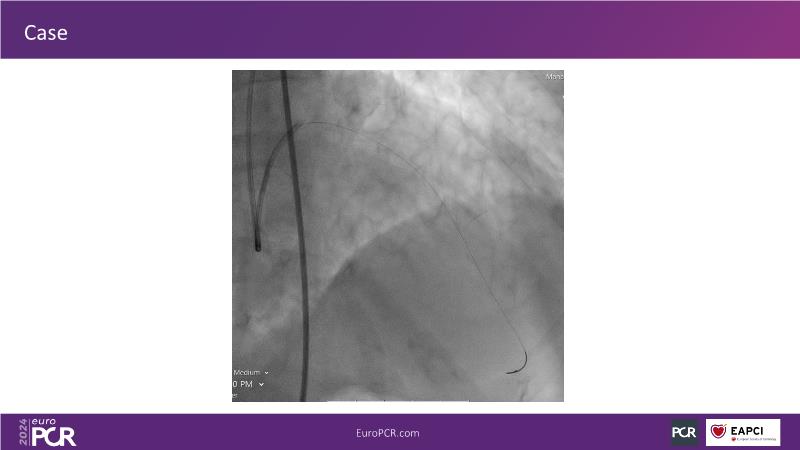

Tune into this 2024 session for insights into the latest ESC guidelines, strategies to prevent and treat no reflow, and an examination of trials like TASTE, TAPAS, and TOTAL on coronary thrombus management. Explore also the outcomes of the CHEETAH study, pondering a potential paradigm shift, and delve into a case study on thrombus removal in a patient with high thrombus burden.